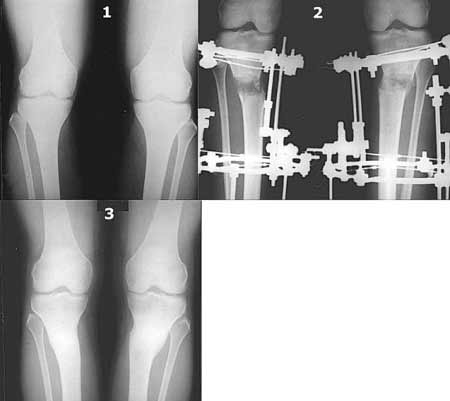

Картинки - в приложении.Будут вопросы - готов ответить.

Ещё картинка - схема. Хотя у Соломина всё написано.

Вот ещё картинки, которые отправлял в Ортопод. Коррекция кривизны и удлинение на 3 см.

1. сначала опирался на опыт лечения ложных

суставов или замедленно сращения - пока малоберцовку не сломаешь - толку не будет.

2. Собственно кривизну по моей статистике исправляют процентов 30, не более. Остальные - либо удлинение, либо и то и другое. Так что уже

наблатыкался ломать - проблем нет.

3. Сломать малоберцовку - чего проще и безвреднее?

4. Если внимательно посмотришь на рентгенограммы, то в зоне перелома малоберцовой кости она втягиваетсмя внутрь, таким образом немного уменьшая объем тканей по внутреннему контуру. Причем чем выше - тем эффектнее. Не надо только совсем высоко лезть - там перонеус. Многих пайциенток это тоже смущает. Так что решаем проблему комплексно. На это, кстати, особо упирает Казбек Кудзаев.